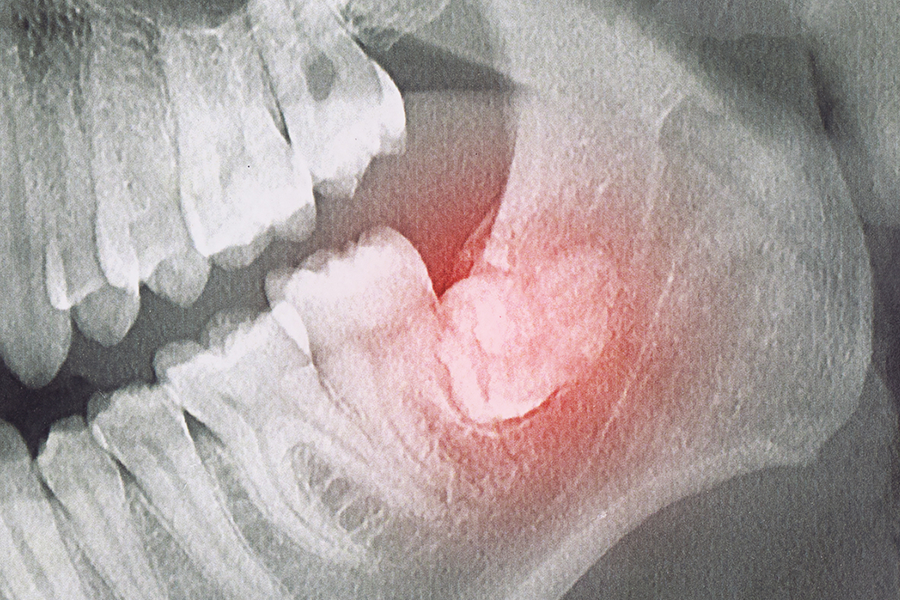

• 04 매복으로 인한 낭종·감염 등 합병증을 조기에 차단합니다.

• 05 X-ray/CT에서 낭종(뼈낭종)·완전 매복이 의심되는 분

음식 끼임·구취가 지속될 때, X-ray/CT에서 낭종이 의심될 때 발치를 고려합니다.